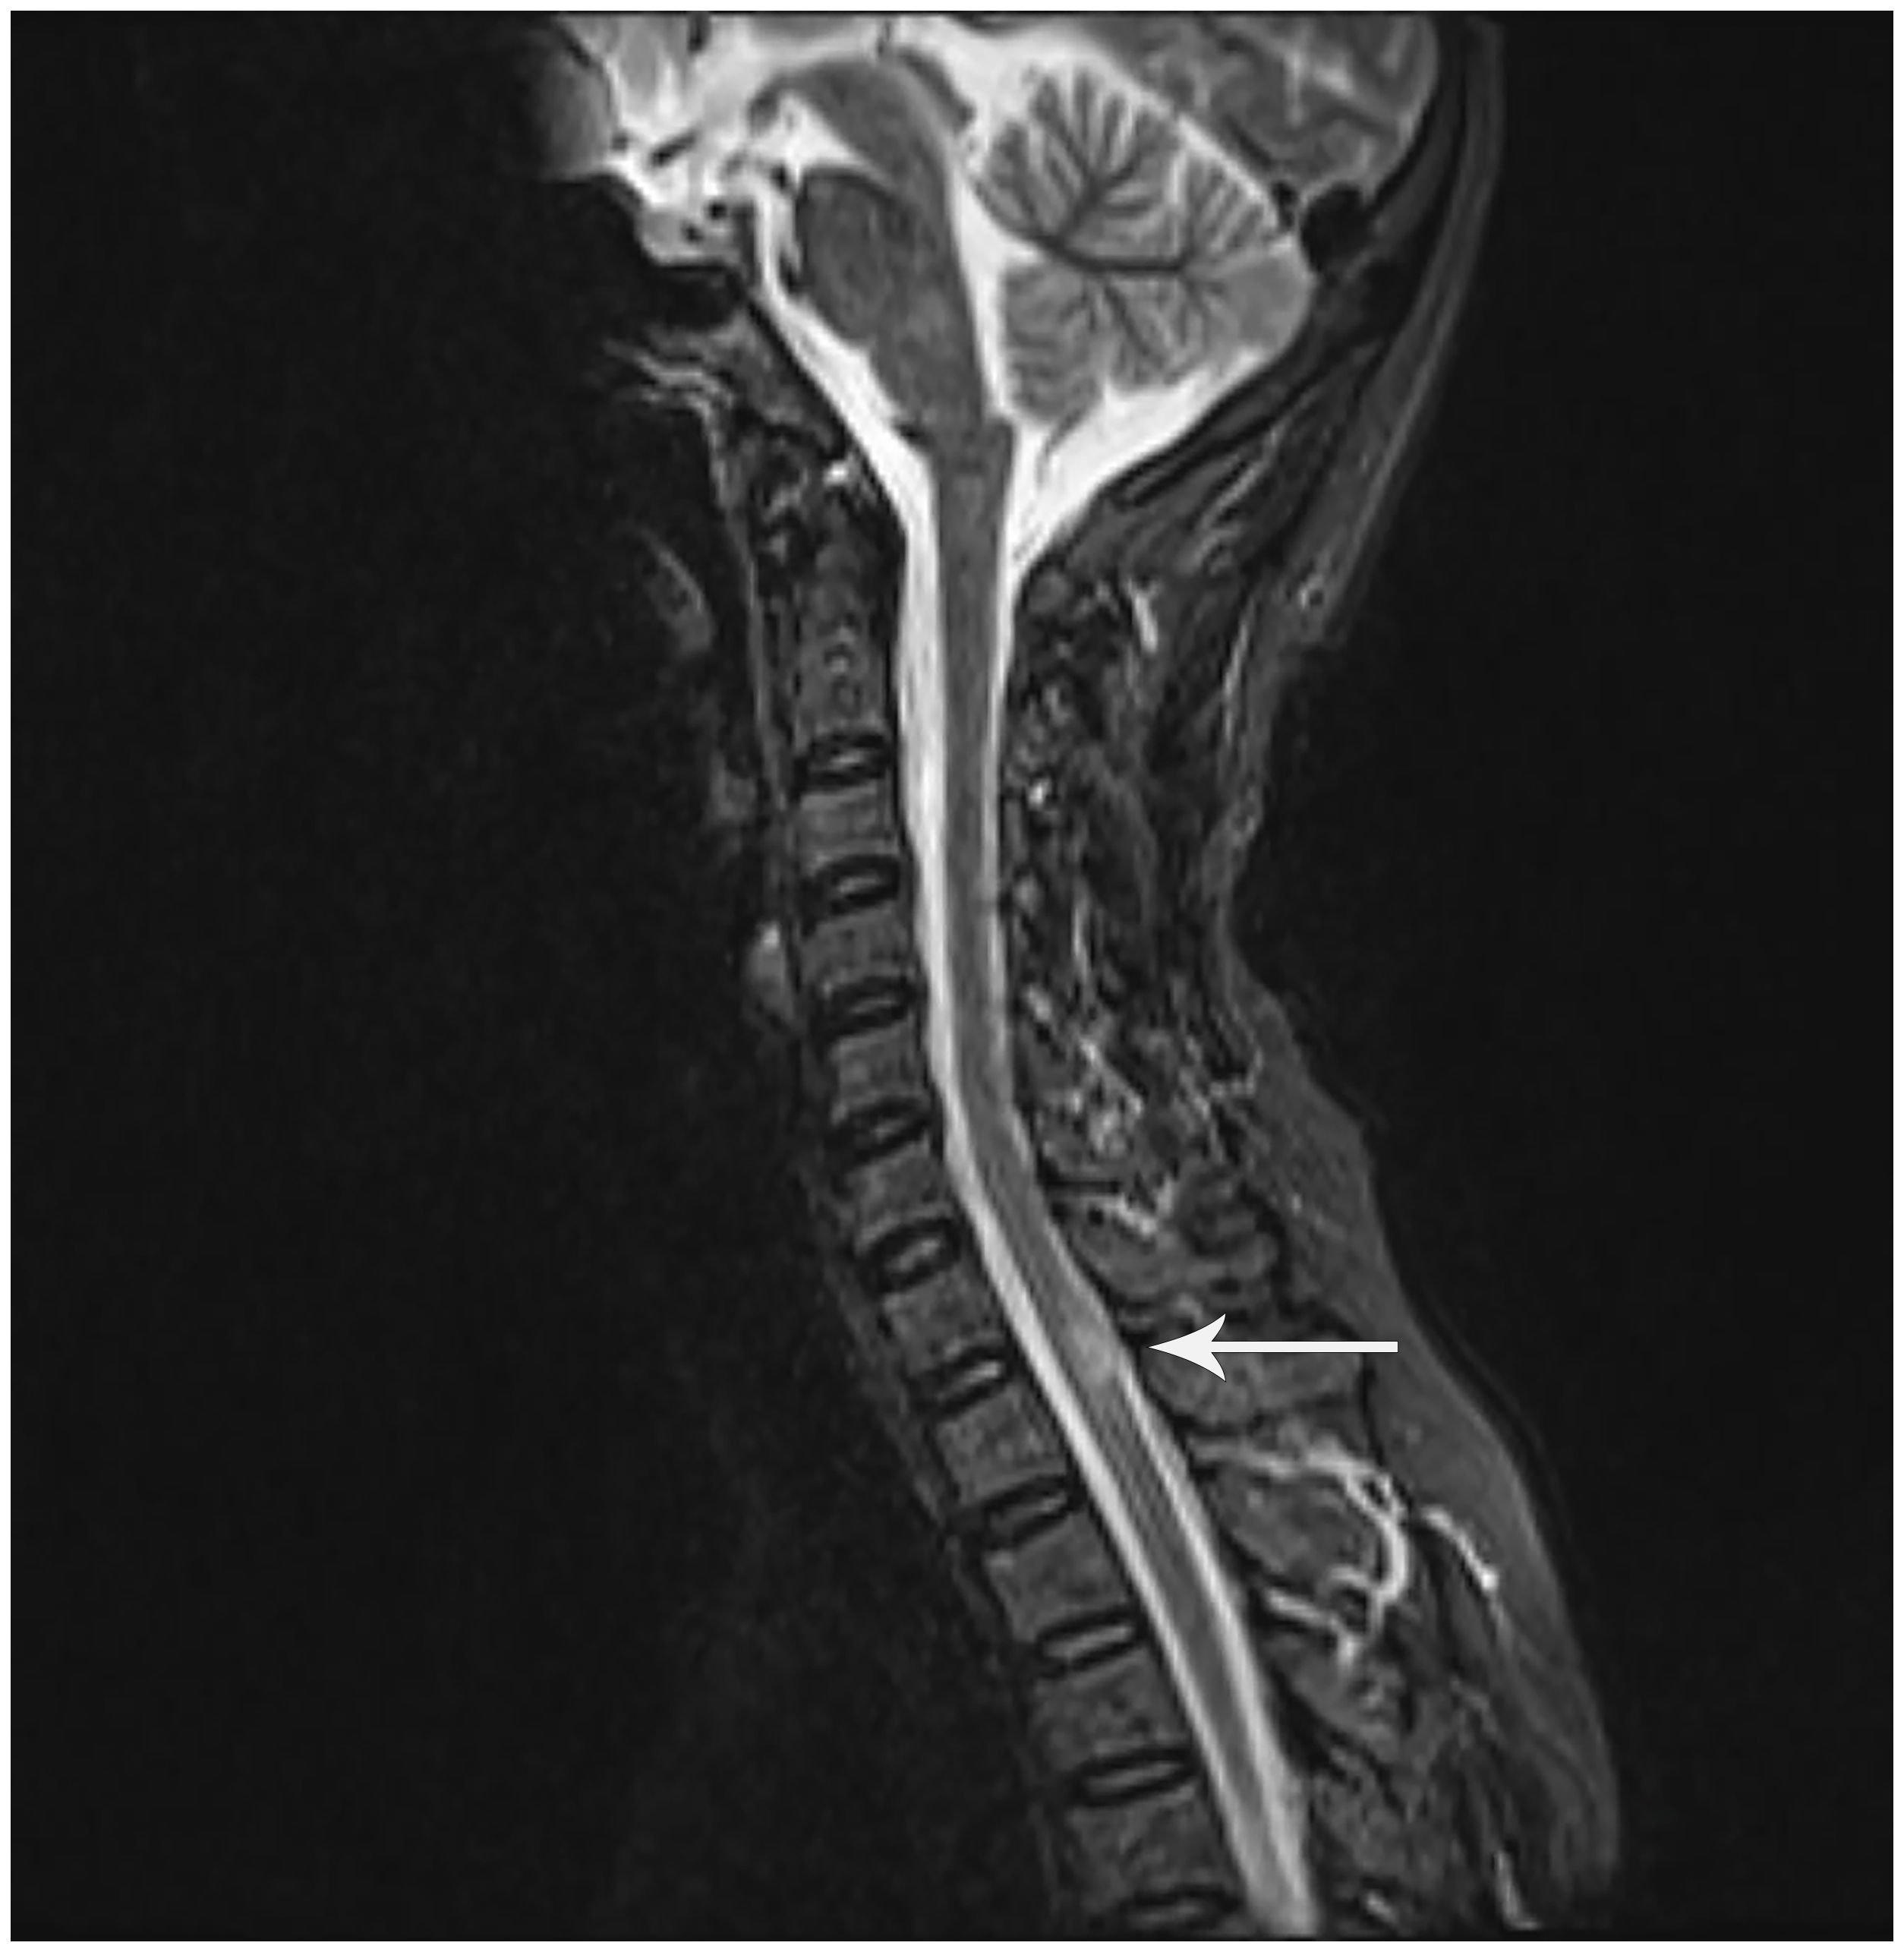

The 48-year-old female patient presented with progressive numbness in the left lower limb in June 2016, which was particularly prominent in the left foot. There was no weakness, blurred vision, dizziness, diplopia, crooked mouth, girdle sensation of the body, or disorders of urination and defecation. Among the ancillary diagnostic studies, magnetic resonance imaging (MRI) demonstrated a focal abnormal signal intensity in the spinal cord at the C7-T1 level, suggestive of a demyelinating lesion (Figure 1). The lumbar puncture indicated normal cerebrospinal fluid (CSF) pressure, with no significant abnormalities in the routine, biochemical, bacterial, cryptococcal, or tuberculosis examinations. Oligoclonal bands (OB) were negative; however, serum AQP4-IgG, as determined by cell-based assay (CBA), was positive with a titer of 1:100. Ultimately, she was diagnosed with NMOSD and received intravenous administration of methylprednisolone (MP) 0.5 grams/day for 5 days. Subsequently, the treatment regimen was adjusted to oral prednisone (Pred) 35 mg/day and azathioprine (AZA) 25 mg/day. Due to hepatic impairment, the Pred dosage was reduced to 5 mg/day, and the AZA dosage was increased to 50 mg/day.

Figure 1. Sagittal T2-weighted MRI of the cervicothoracic spine: A hyperintense lesion at C7-T1 (white arrowhead). Although this lesion does not meet classical LETM criteria (≥3 vertebral segments), NMOSD diagnostic guidelines (Wingerchuk et al., 2015) waive the lesion length requirement for AQP4-IgG-seropositive patients. This clinically compatible lesion correlates with left lower limb numbness.

The spinal lesion in this case did not meet classical imaging criteria for longitudinally extensive transverse myelitis (LETM). However, diagnostic guidelines permit exemption from spinal lesion length requirements in AQP4-IgG seropositive patients (3). The temporospatial correlation between progressive left lower limb numbness and a focal demyelinating lesion at C7-T1 satisfied acute myelitis criteria. Lumbar puncture demonstrated absent OB with normal CSF parameters, providing critical laboratory evidence against multiple sclerosis and supporting NMOSD. The recurrent hiccups and vomiting in 2018, consistent with area postrema syndrome—a core NMOSD clinical phenotype—further confirmed the diagnosis.